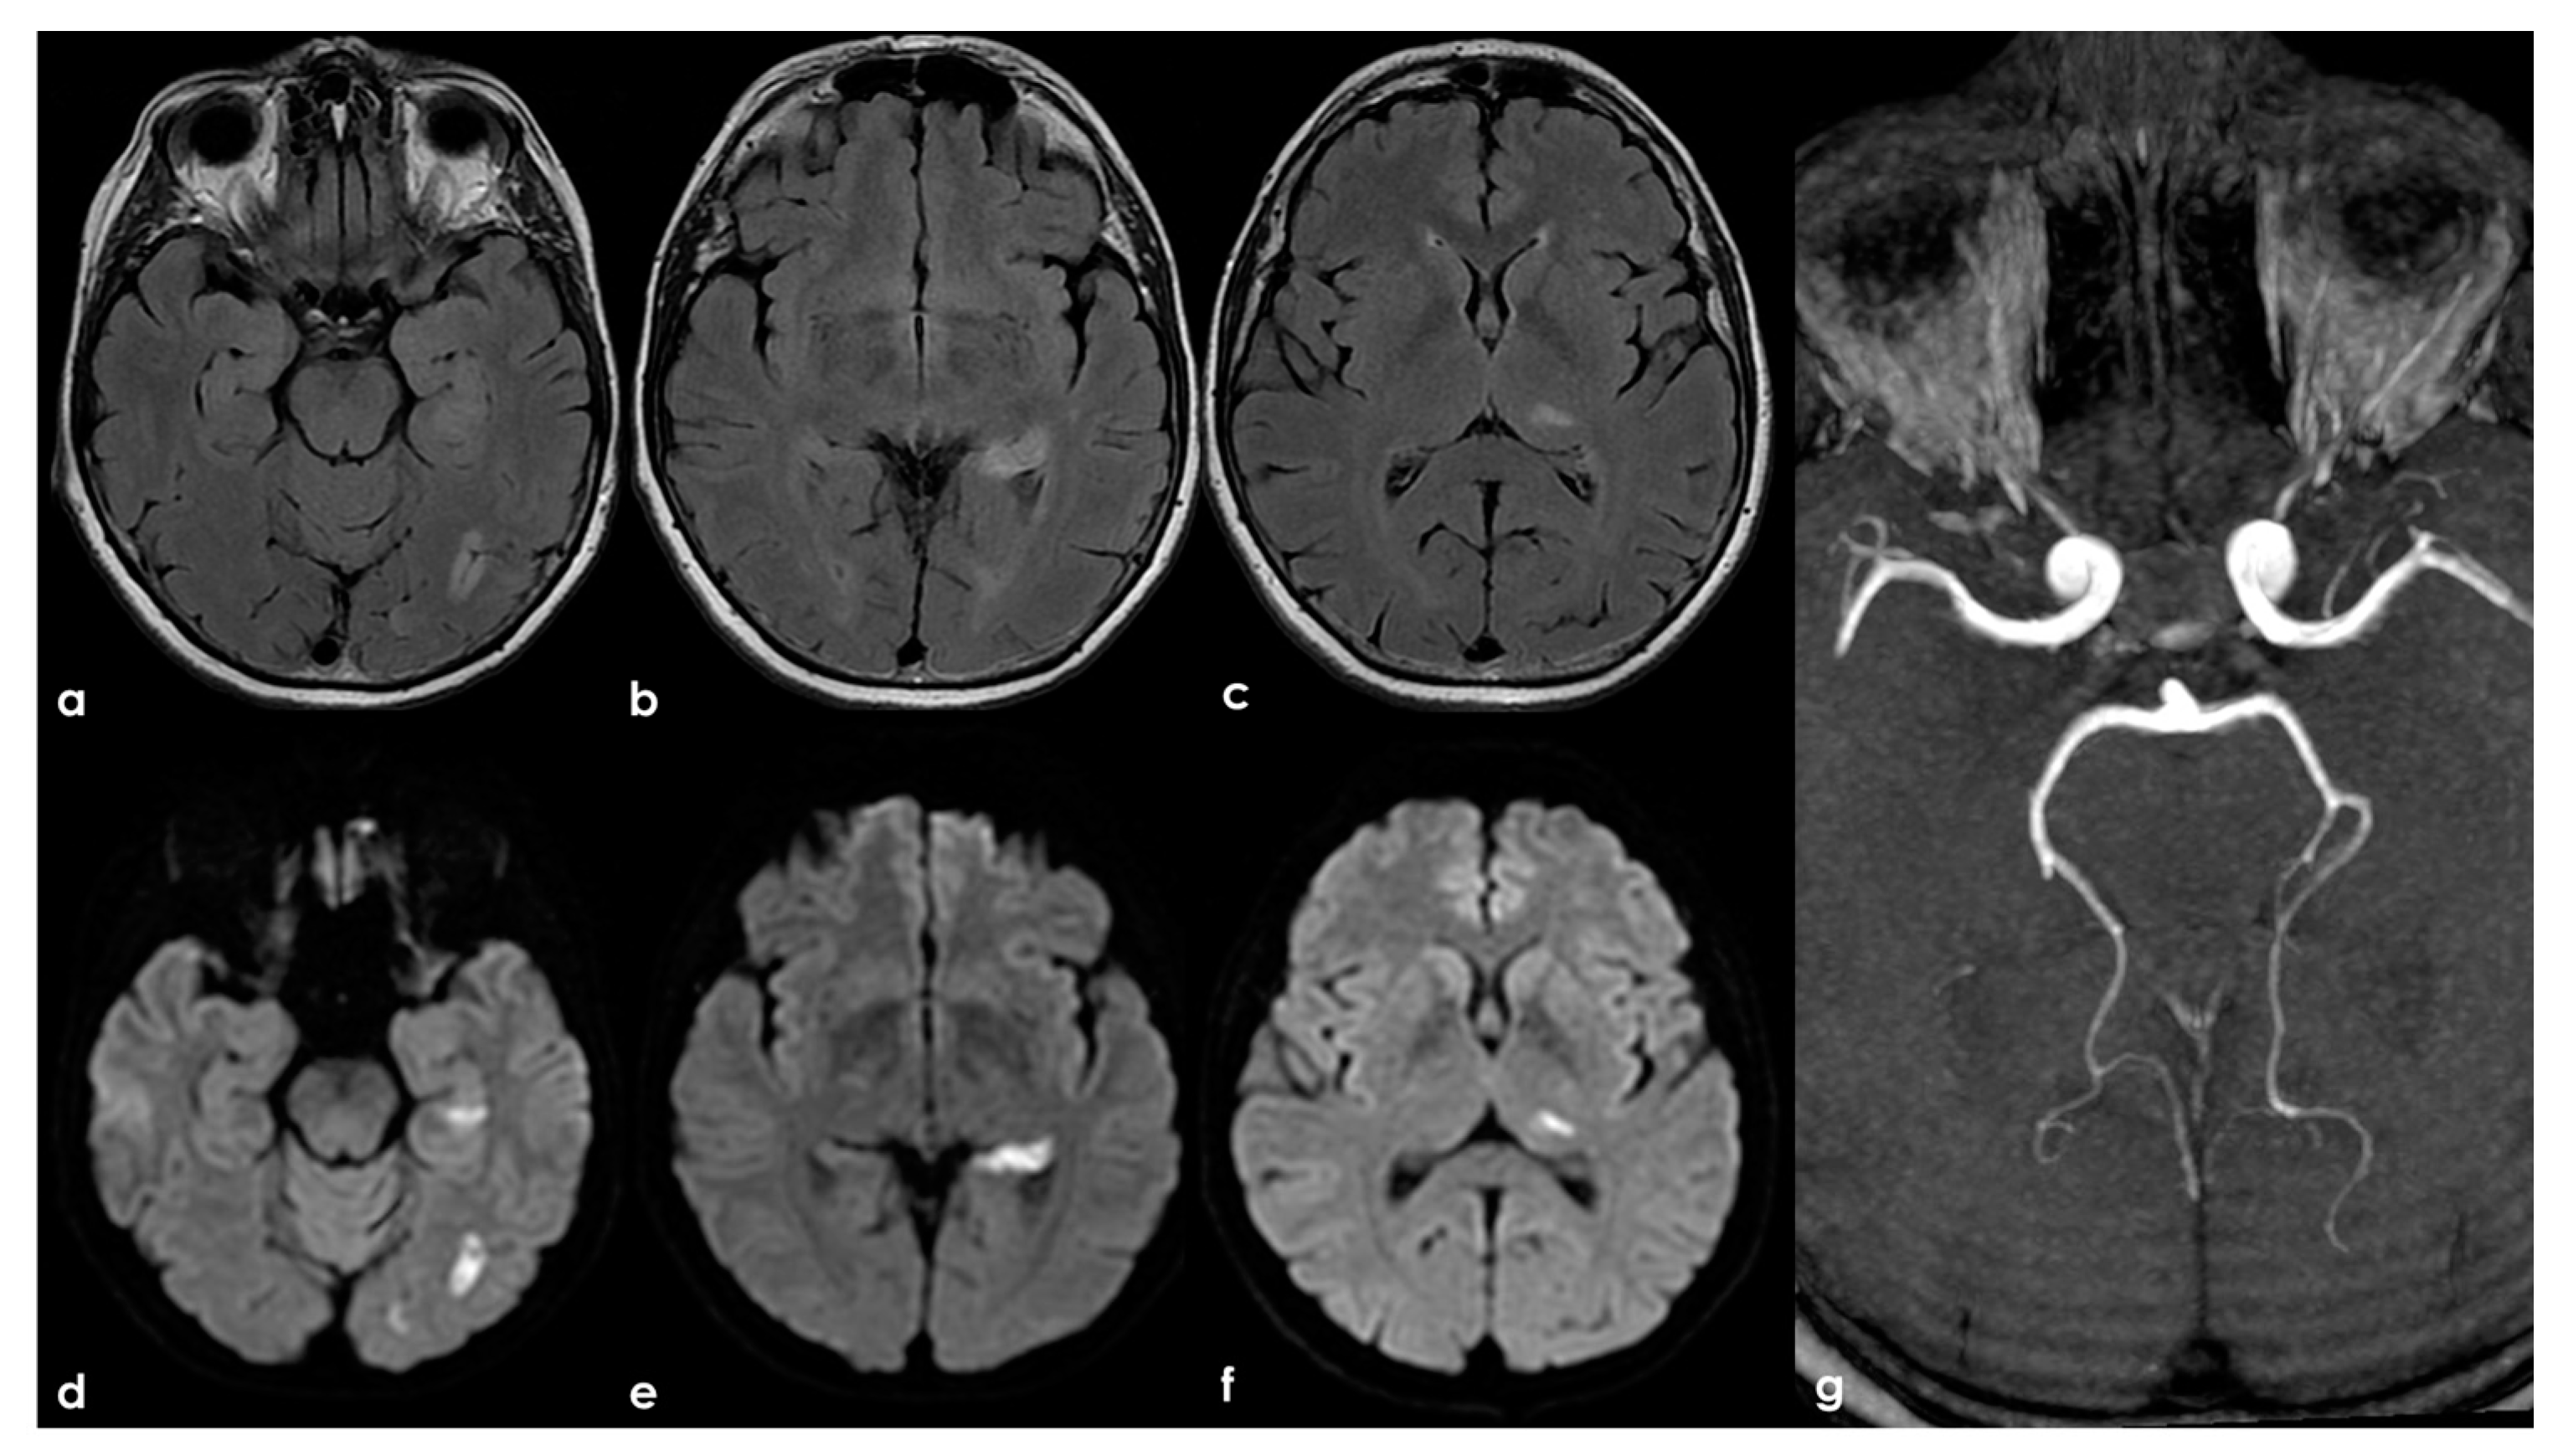

Figure 5.

An example of multifocal cerebellar ischemic lesions in a patient with APS (double positivity). Brain MRI (axial FLAIR in (a,b), coronal T2W sequence in (c) shows the poromalacic evolution of multiple ischemic lesions involving both cerebellar hemispheres (right ≥ left). No causes other than APS were identified in this patients.

In addition, Figure 6 shows the presence of multiple ischemic lesions in the same arterial territory, and this issue has not been clearly addressed in the multiplicity of lesions described in the abovementioned paper [].

Figure 6.

Brain MRI (axial FLAIR in panels (a–c) and the corresponding DWI slices in panels (d–f)) showing multifocal ischemic lesions in the left PCA territory with a patent PCA on MRA (panel (g)).